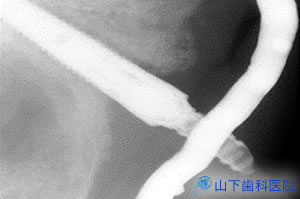

| そこであえて無用なCT撮影は行わず、触れて顎骨形態の特徴を細かく把握し、通常の石膏模型、通常のレントゲン画像を参考に、総入れ歯を透明レジンに置き換えて複製したものを石膏模型上で改造、ガイドのずれを止める固定用アンカーピンはノーベルガイドのものを利用する写真のようなインプラント埋入用自家製ガイドを作りました。 | ![]() |